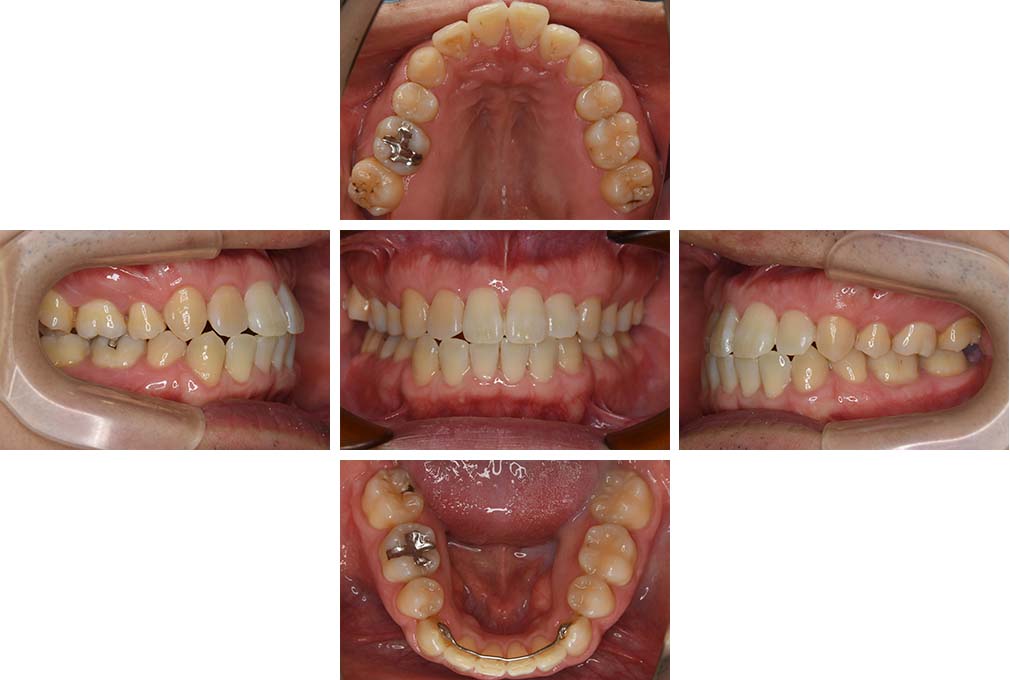

CASE:03

上下顎前突

初診時年齢 18歳4か月

性別 男性

治療費の目安 105万円程度(治療開始時)

歯列の乱れは著しくなく上顎右側側切歯が捻転し口蓋側へ転位していた。また、問診の中で患者さんから最も重視する治療結果として口元の突出の改善の申出があった。下顎が後退した上顎前突傾向ではあったが著しいものではなかった。上下顎前突と診断し上下顎小臼歯抜歯を行っていただき、上下顎舌側マルチブラケット装置を使用して、矯正用アンカースクリューを併用して動的治療を行った。上下顎前歯の後退を十分行い口元の突出感も改善した。治療後10年1か月の来院時には口元の突出感が再発することもなく、下顎前歯の少しの唇舌的なずれはあったが歯列は安定していた。動的治療期間2年2ヵ月間。

治療前

18歳4ヵ月

治療後

動的治療期間2年2カ月間

20歳10か月

10年経過

動的治療終了後10年1カ月

30歳11か月